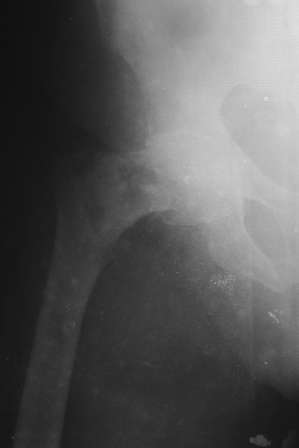

Сегодня оперировал, остеосинтез 130-град. Г-образной пластиной, из-за наступившийся трешины б/вертела дополнительно спонгиозным винтом, вроде неплохо получилось. Проблема с фотоаппаратом, как получится отправлю снимки.

Всем огромное спасибо! К стати исползовал дистракционный метод А.Н. Челнокова, очень удобно и легко работать! Спасибо Саша и Джолдас!!

Прилагается п/о рентген снимок.